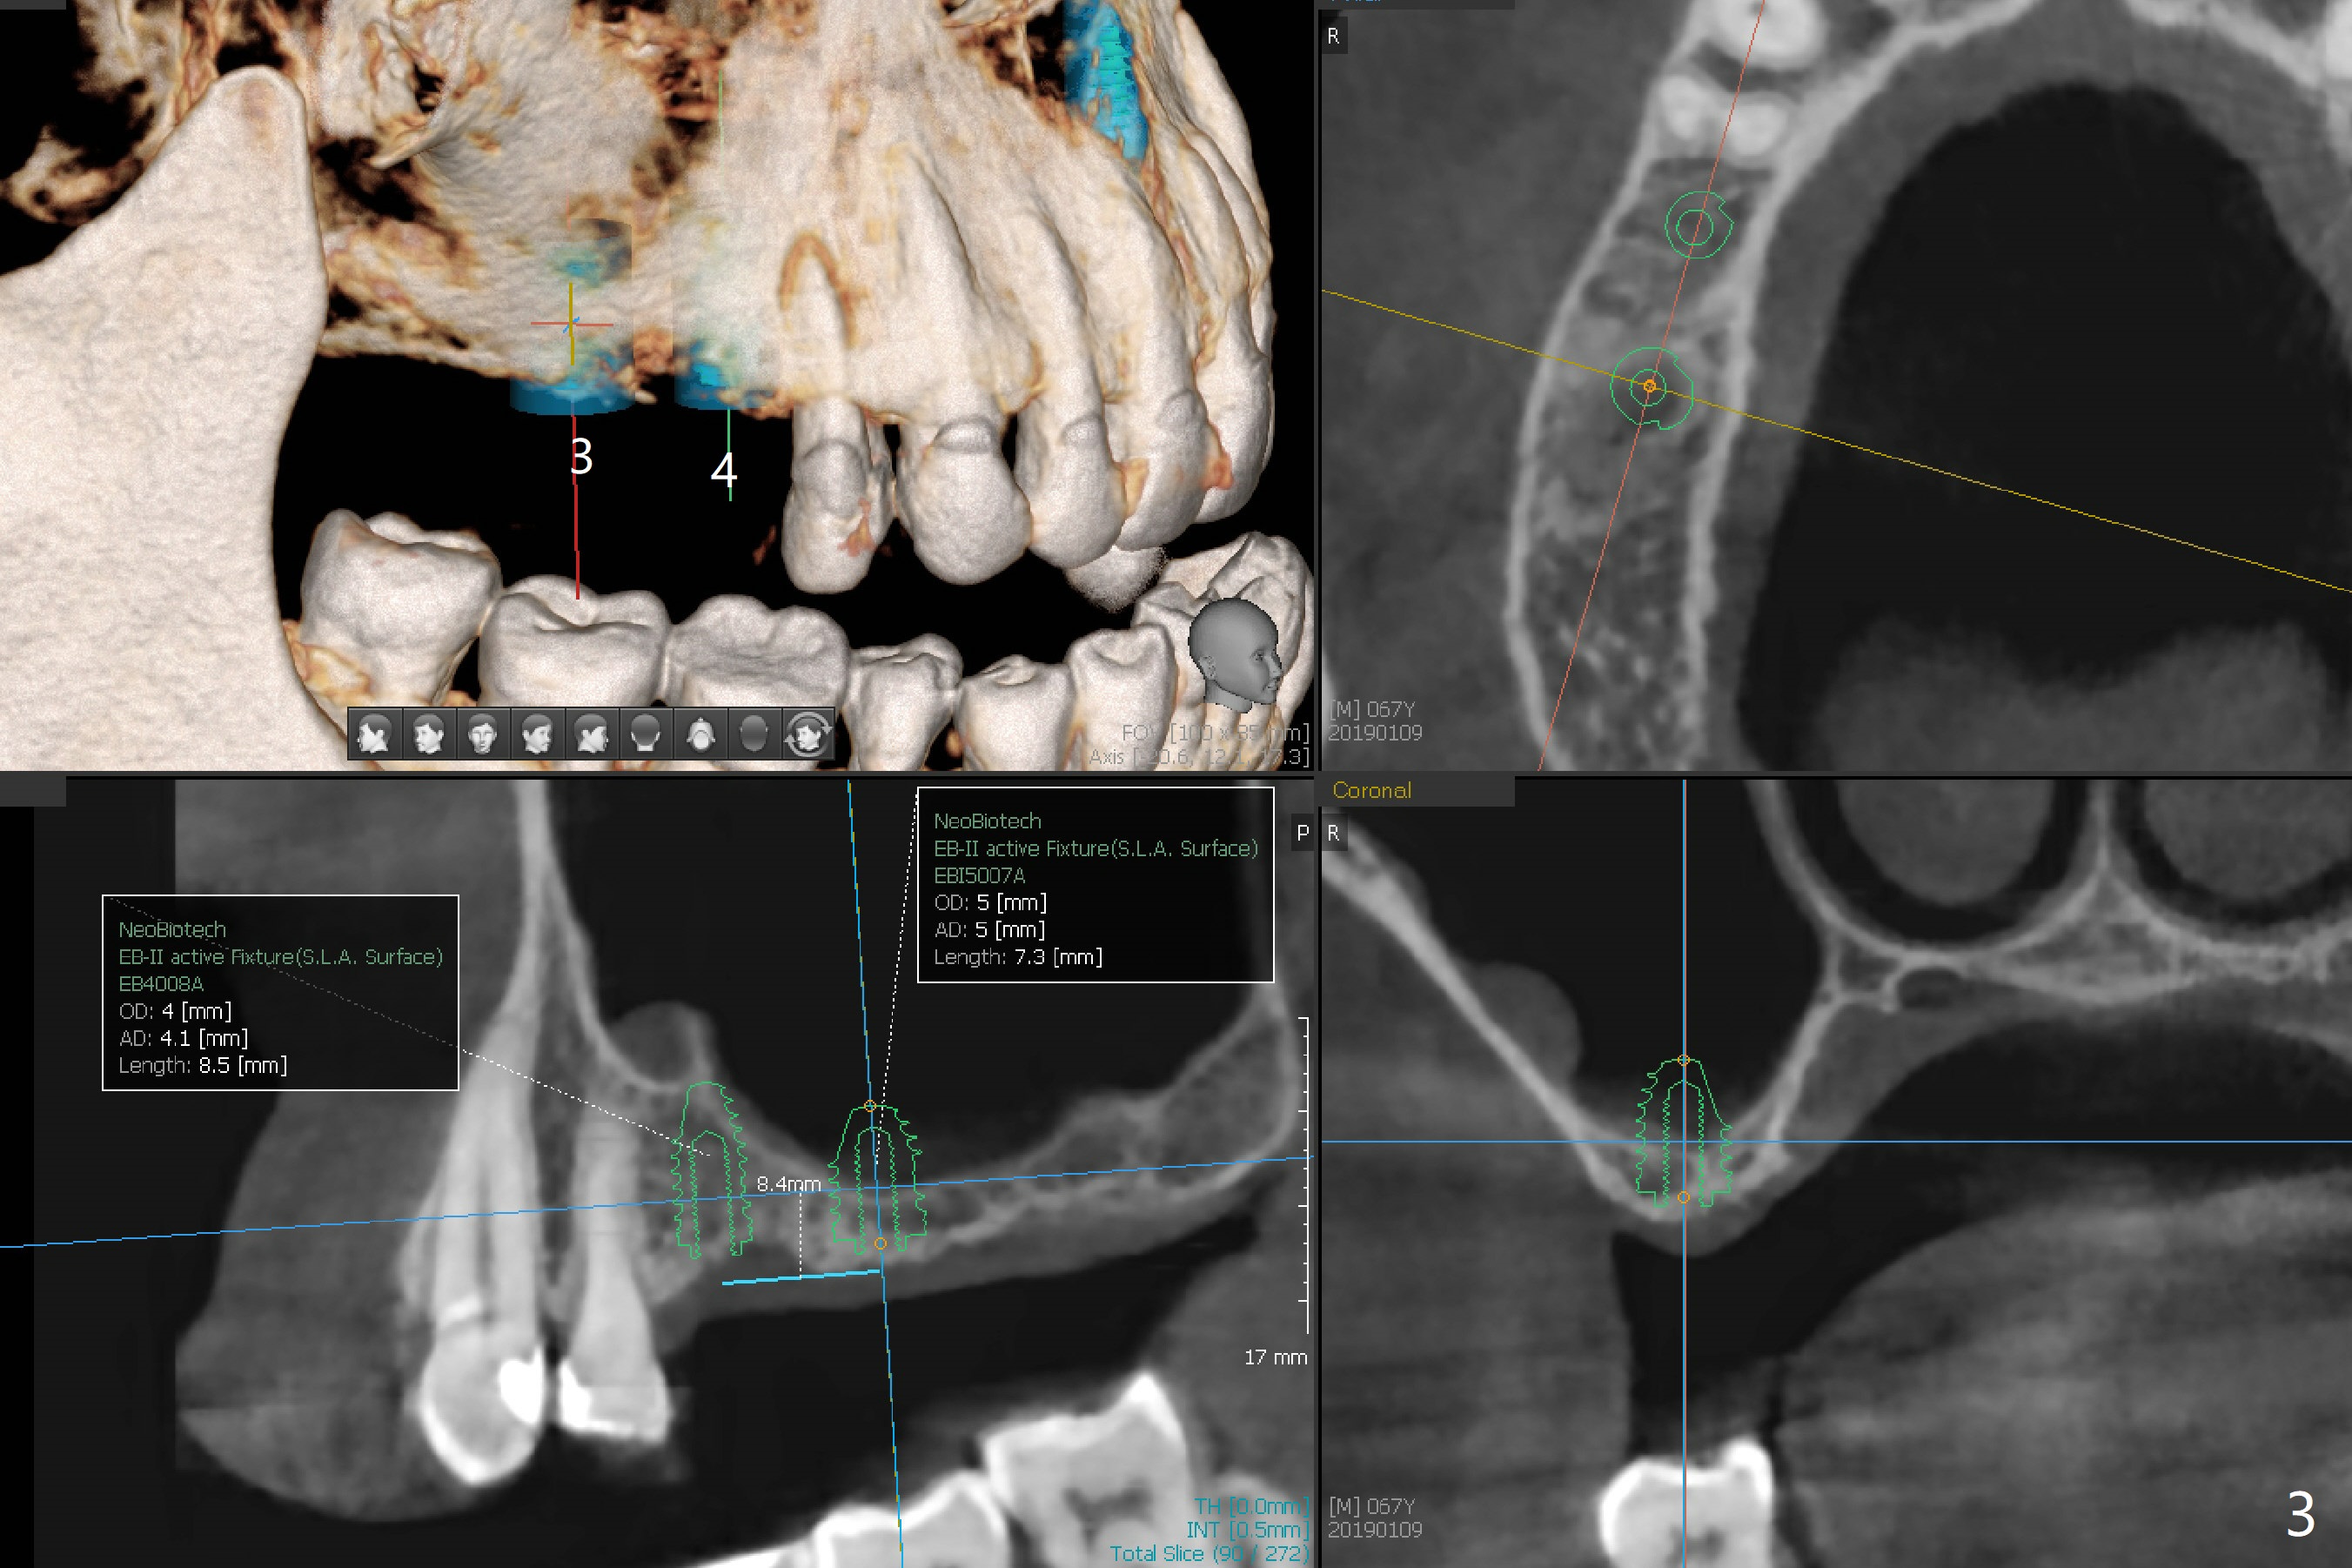

A 63-year-old woman wants to change upper RPD (for #2-4, 13 and 14) to implants because of denture-associated candidiasis. She is afraid of osteoporosis, although the implant at #18 is doing fine almost 3 months post cementation (Fig.1). One way to restore the upper right quadrant is to place 3 short implants (7.3 or 8.5 mm) with guide with simultaneous internal or external sinus lift (Fig.2-4). The tooth #12 appears to have root fracture with periradicular radiolucency (Fig.5); an immediate implant will be placed. While a short implant will be placed at #13, no implant will be placed at #14 because of 1 mm bone (Fig.6). A cantilever FPD will be fabricated in the upper left quadrant. The thick left sinus membrane is a problem as related to a lift?